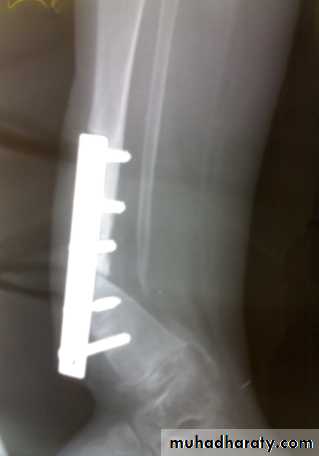

Displaced and/ or comminuted lateral or medial tibial condyle fracture

Treatment:ORIF.

Associated ligament injury repaired.

Bicondylar fracture: needs ORIF with plate and screws or external fixation.